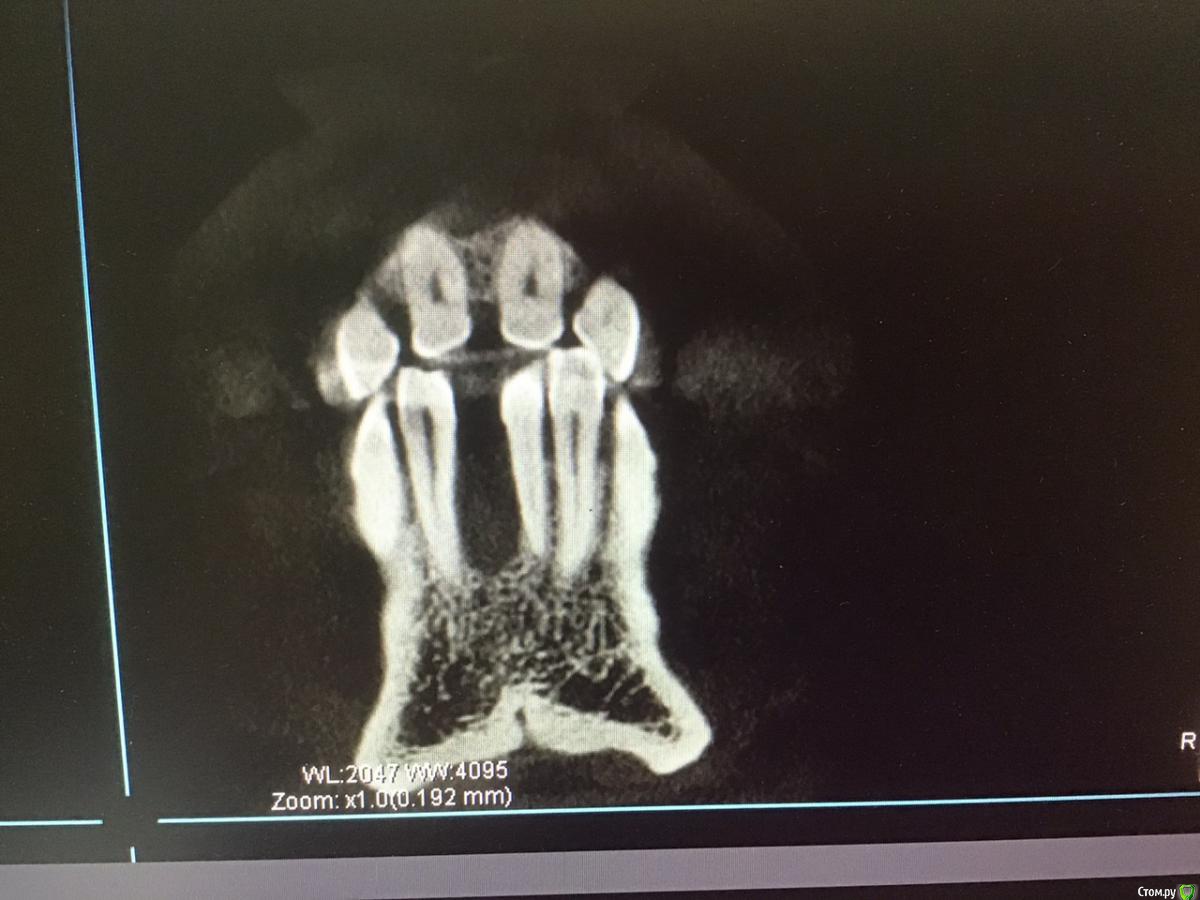

4lev Опубликовано 20 ноября, 2019 Поделиться Опубликовано 20 ноября, 2019 Здравствуйте! Хотелось бы получить совет. Были в 5 клиниках и все планы лечения разные. Нижняя челюсть. Справа все единодушны, а вот слева и во фронтальной зоне разногласия, боимся ошибиться. Пациент мужчина, 67 лет. Сделано КТ в одной из клиник, другие говорят, что плохое качество. Можно ли по этому исследованию принять решение? Заранее спасибо. Владимир.Ссылка для скачивания файлов: https://cloud.mail.ru/stock/iNXKZVqLzRqyfXzwbHJzDMVi . Ссылка на комментарий

4lev Опубликовано 20 ноября, 2019 Автор Поделиться Опубликовано 20 ноября, 2019 Справа внизу все единодушно предлагают 2 импланта.Слева варианты: 1.поставить 2 импланта с костной пластикой (стружка) у 7 зуба во время операции. 2. поставить только один имплант(6), так как для 7 недостаточно костной ткани и он не особо нужен. 3. поставить два импланта потом, когда восстановится кость после удаления зуба( а это было летом), а пока принимать кальций. Теперь впереди: 1. поставить один имплант. 2. удалить один зуб и поставить два импланта. 3. удалить три зуба и сделать мост на двух имплантах. В общем, предлагают эти варианты в разных комбинациях, голова кругом и не знаем какой вариант оптимальный. Еще в одном варианте предложено подпилить 2 верхних зуба, которые опустились и поставить на них циркониевые коронки, по 2 слева и справа. Буду благодарен за советы. Ссылка на комментарий

4lev Опубликовано 20 ноября, 2019 Автор Поделиться Опубликовано 20 ноября, 2019 Получилось только так, к сожалению Ссылка на комментарий